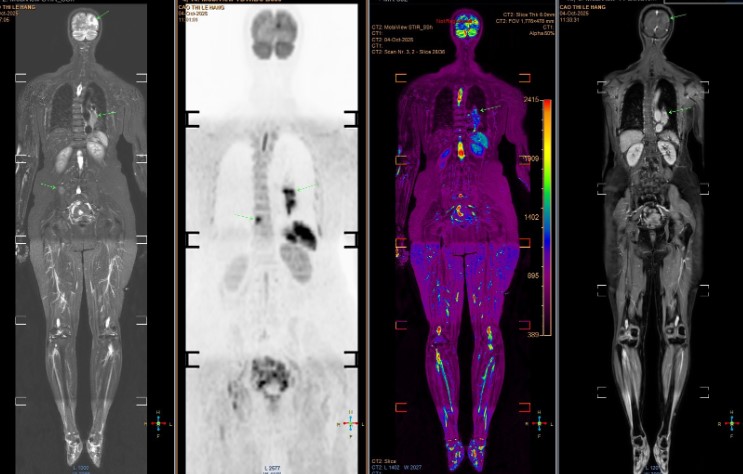

Qua chụp MRI sọ não, bác sĩ phát hiện bệnh nhân có nhiều ổ tổn thương di căn dạng biểu mô tuyến. Nghi ngờ di căn từ phổi hoặc đại tràng, bà được chụp CT phổi và phát hiện khối u UT phổi lớn ở đáy phổi trái. Đáng tiếc, UT đã di căn lên não, cột sống và xương chậu, tiên lượng xấu.

Hình ảnh chụp phát hiện nhiều tổn thương di căn.

Giáo sư Khoa lo ngại về tỷ lệ thanh thiếu niên sử dụng thuốc lá và thuốc lá mới (như thuốc lá điện tử) vẫn ở mức cao, làm gia tăng nguy cơ UT phổi trong tương lai. Ông khuyến nghị tầm soát sớm cho những người có nguy cơ cao, như người hút thuốc chủ động hoặc thụ động. Chụp CT liều thấp có thể phát hiện tổn thương nhỏ, trong khi các kỹ thuật hiện đại như PET/CT, PET/MRI, kết hợp sinh học phân tử, giúp xác định đột biến gene và lựa chọn điều trị trúng đích hiệu quả.